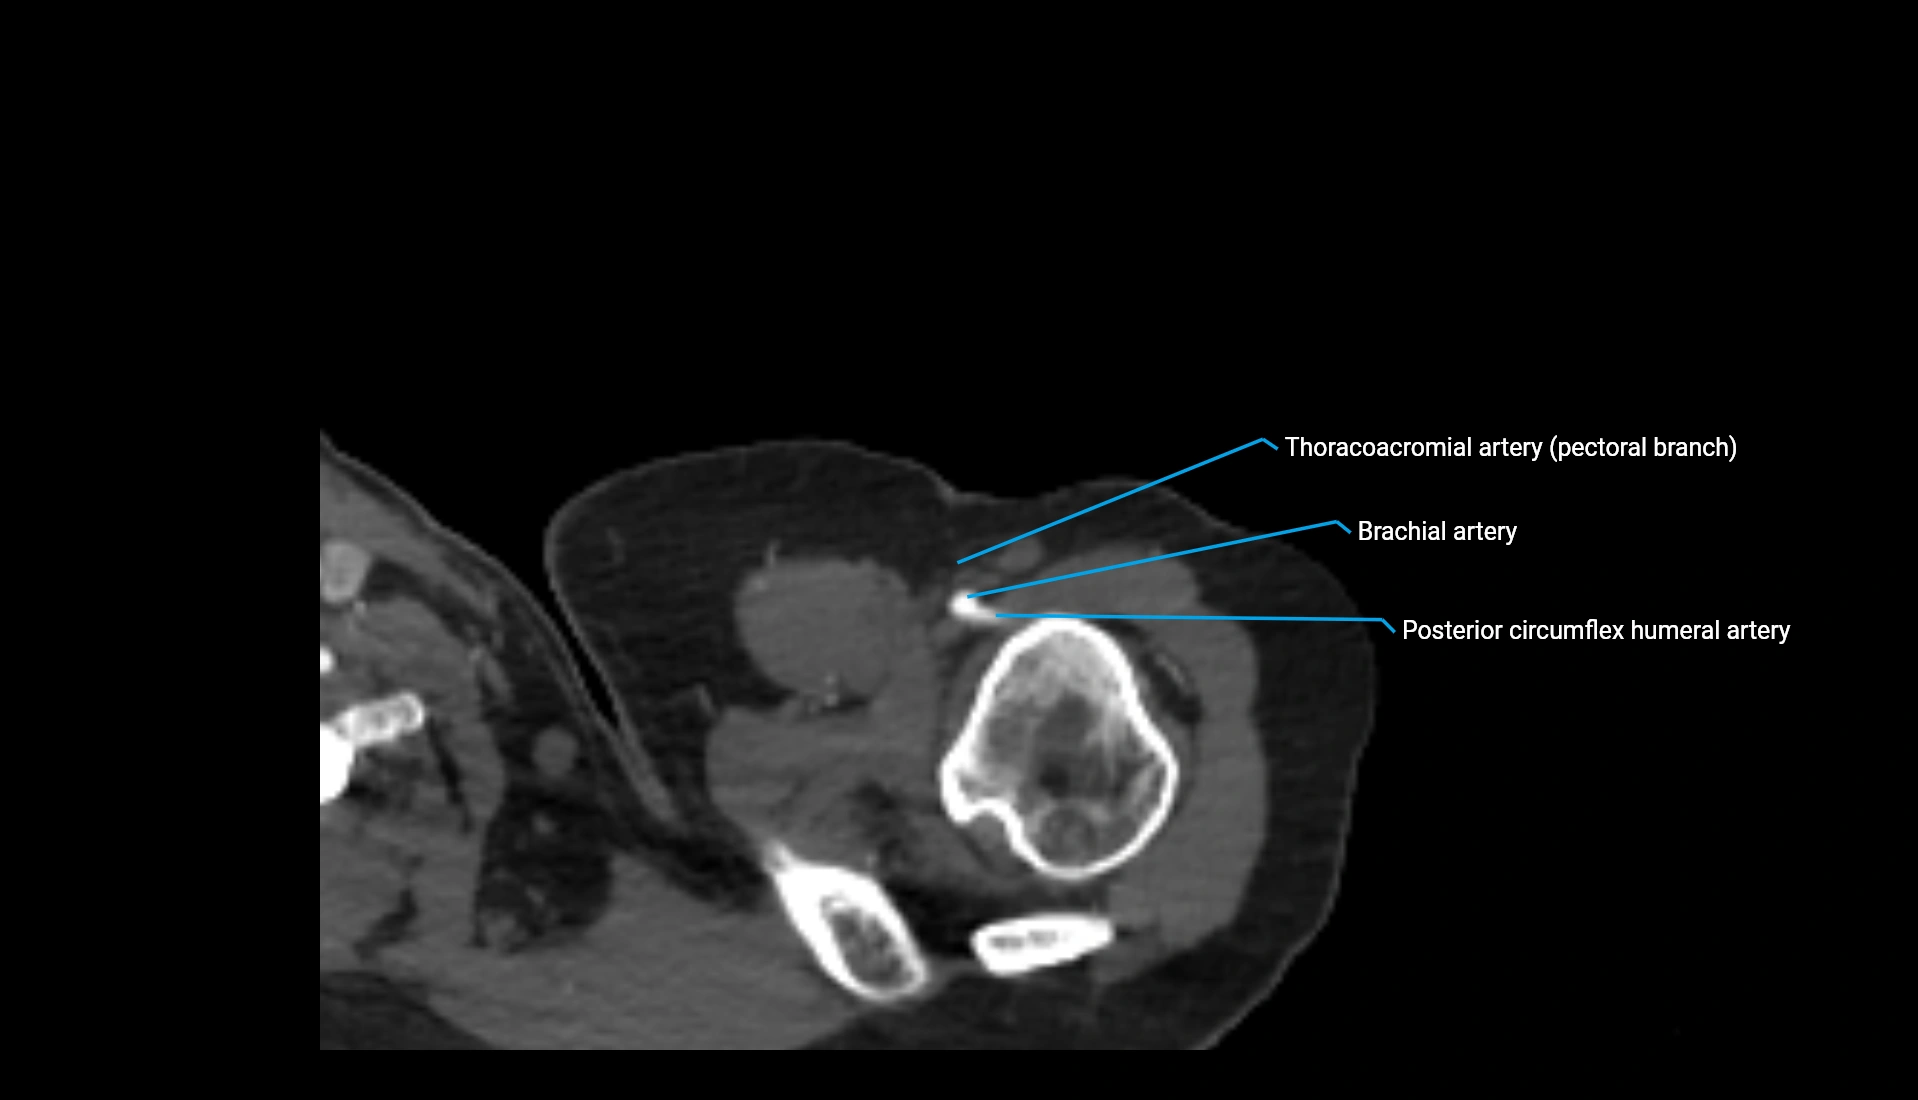

CT Appearance

Non-Contrast CT:

• Cortex: High-density, sharply defined

• Subchondral bone: Dense cancellous matrix

• Articular surface: Smooth concave contour articulating with the capitellum

• Excellent for evaluating bone integrity, alignment, and subtle fractures